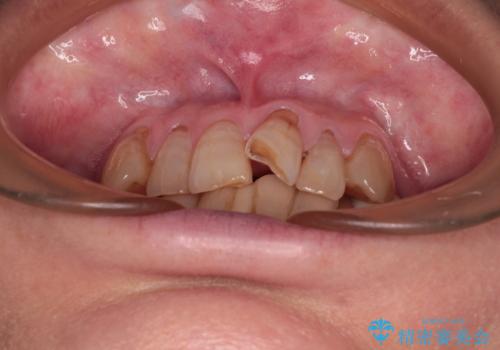

- 長年気にしていた捻れた前歯が欠けたとのことで来院された患者様です。

矯正治療に抵抗があったそうですが、前歯が欠けたことをきっかけに、矯正治療で歯列を整えた上で、セラミッククラウン治療を行う決心が付いたとのことでした。

デコボコが強いため、ブリッジや残根となっている部分のスペースを利用して歯列を整え、変色や欠けている歯をオールセラミッククラウンによる補綴治療を行うこととしました。